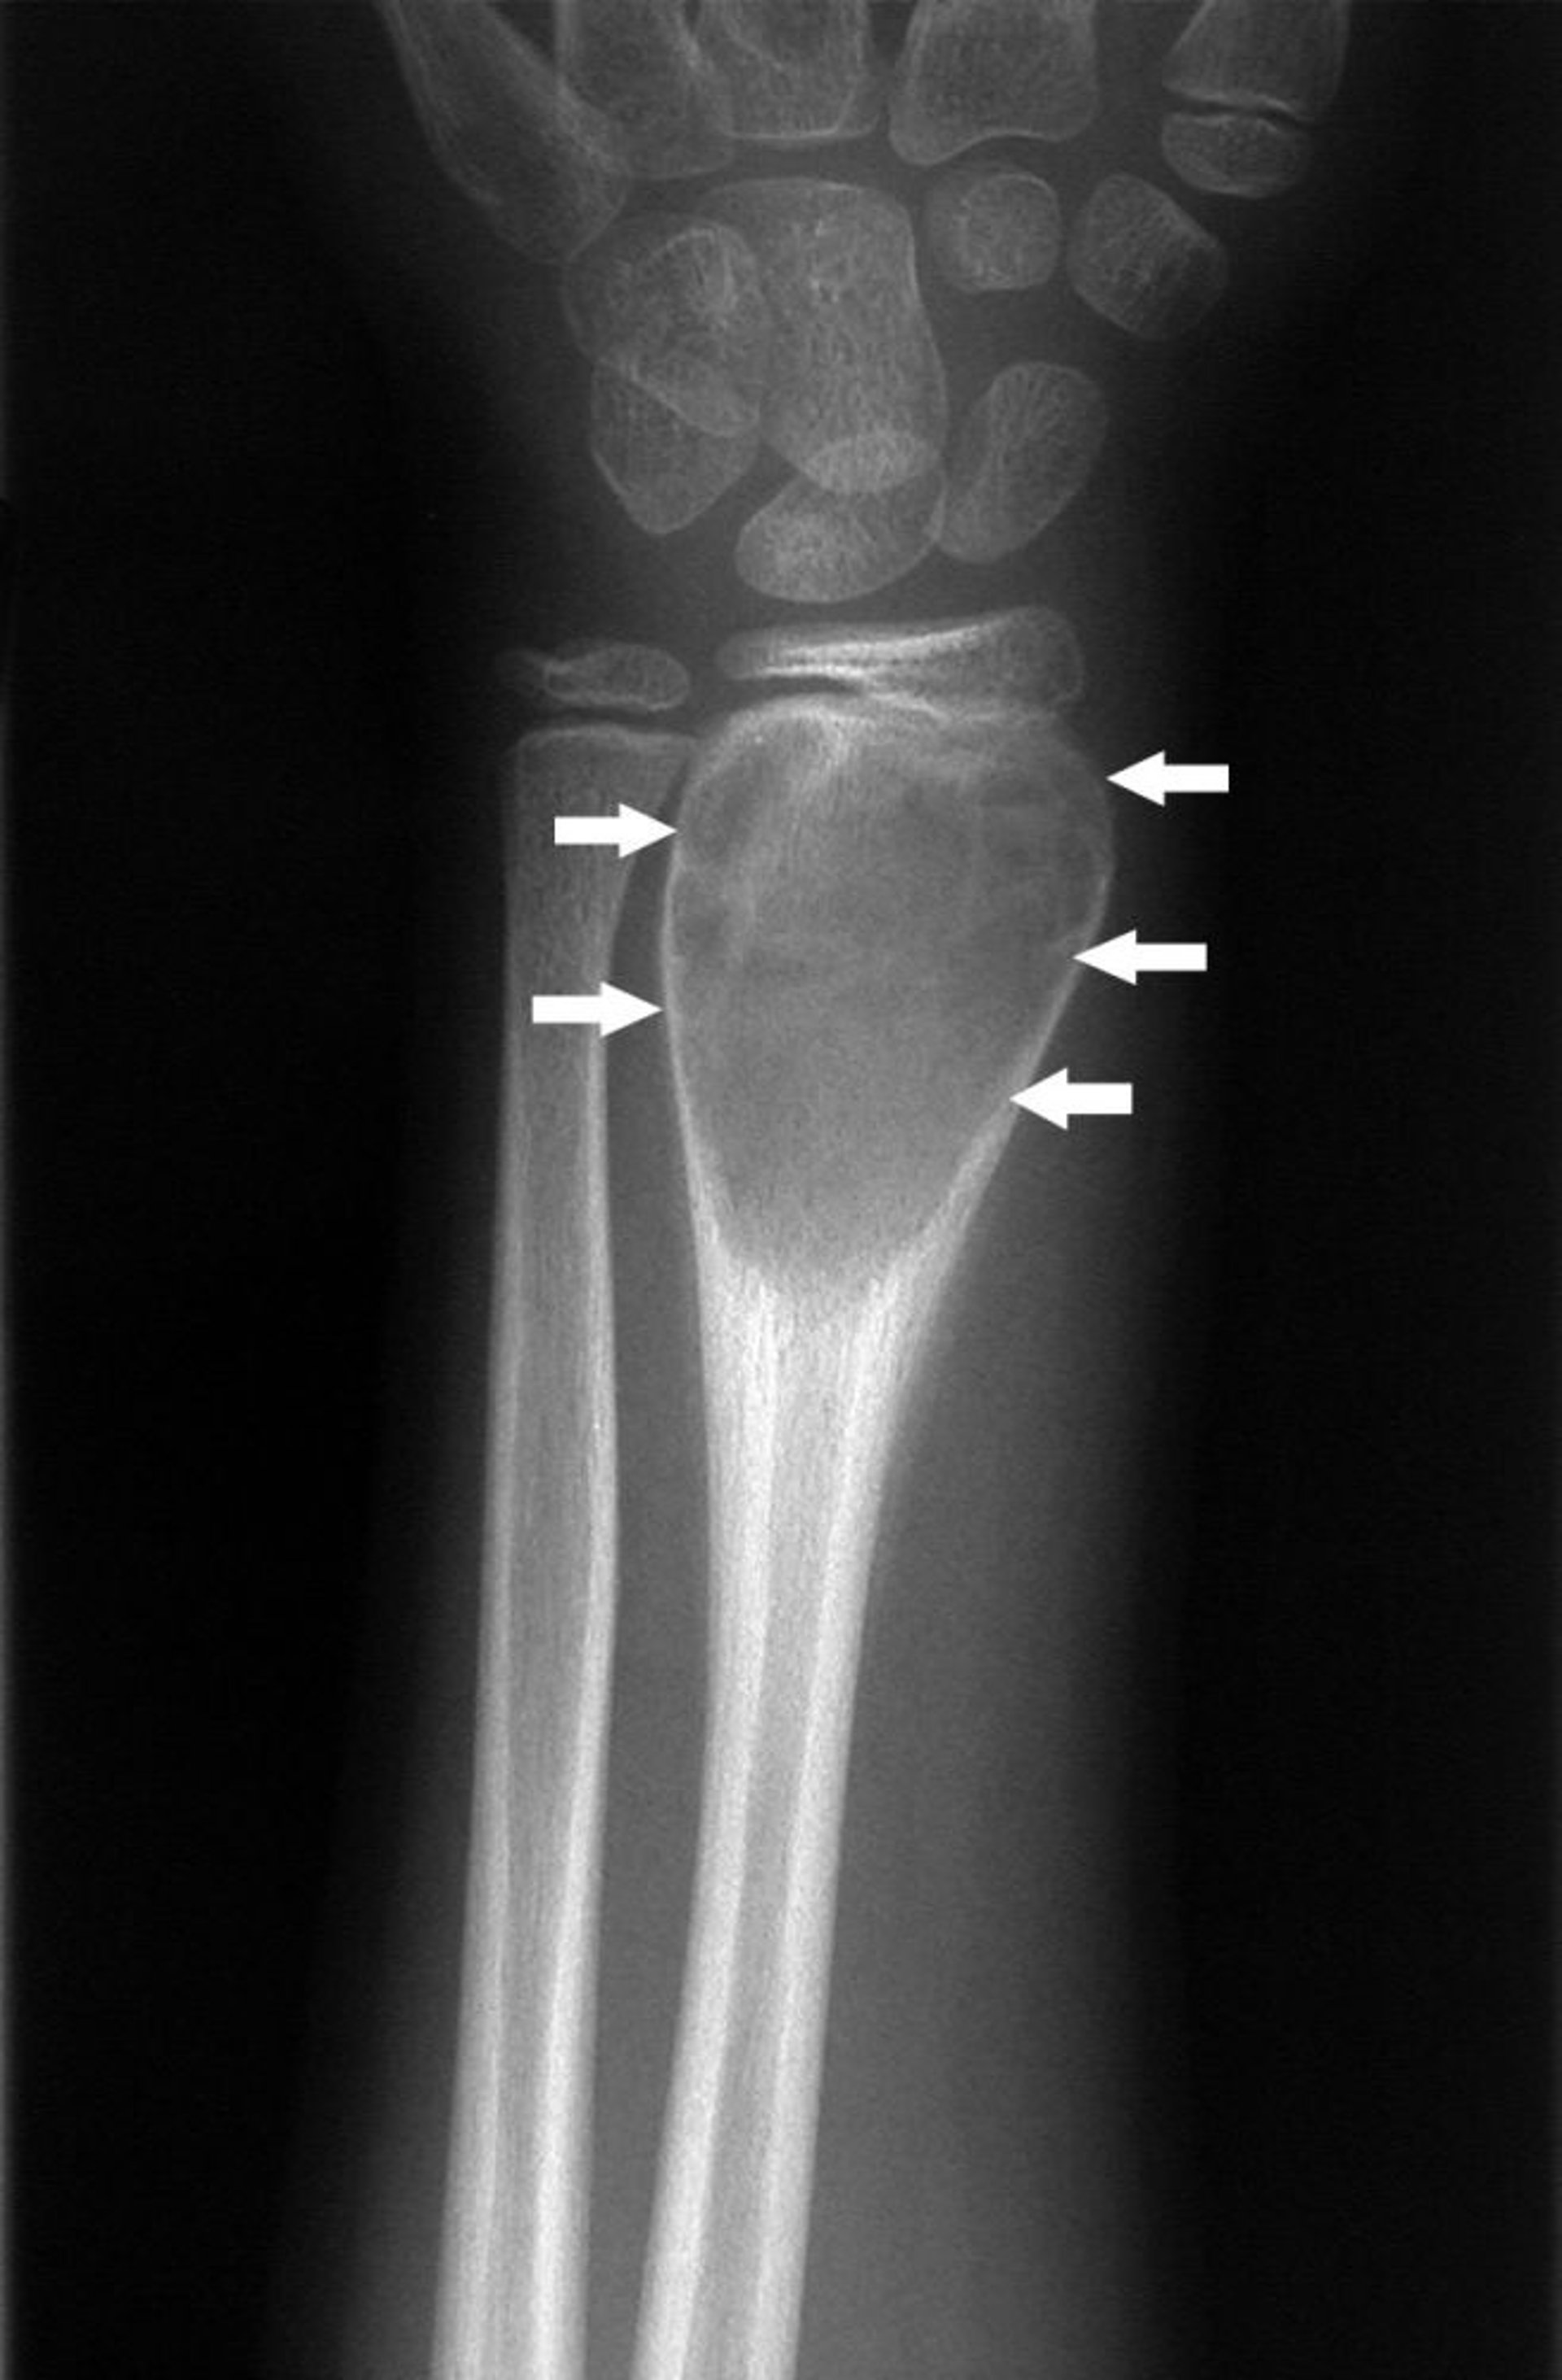

Аневризматическая костная киста запястья

На этом рентгеновском снимке запястья показано периостальное образование новой кости вокруг экспансивного поражения (стрелки), что является характерным для аневризмальной костной кисты.

Image courtesy of Michael J. Joyce, MD, and Hakan Ilaslan, MD.